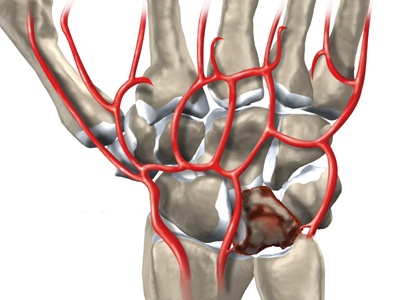

Некроз полулунной кости при болезни Кинбека